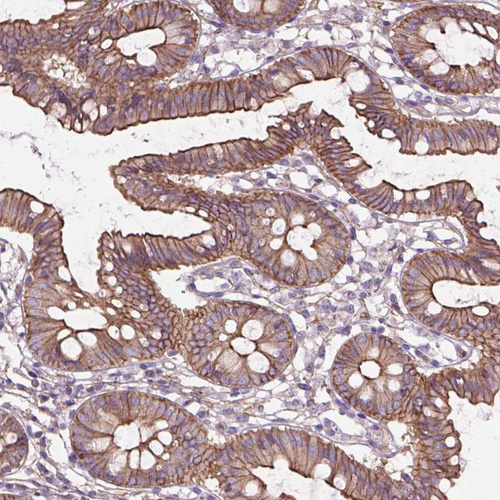

Immunohistochemical staining of human colon shows strong membranous positivity in glandular cells.